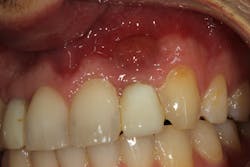

• Site development to increase hard and soft tissue for pontic sites in fixed bridge prosthetics (figures 4–4e)

• Rebuild defects around adjacent teeth after extracting teeth due to periodontal disease (figures 5a–5c)